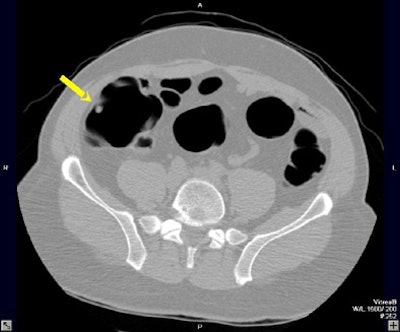

| A 6- to 9-mm adenoma in the ascending colon was missed due to perceptual error. Above supine axial image through the ascending colon. The arrow points to a 6- to 9-mm polyp, which was not seen on the initial interpretation. Below, 3D endoluminal view shows the polyp (arrow) on a fold. Images courtesy of Dr. Eric Paulson. |

Ten of the 13 perceptual errors were "flat-out misses" in which the lesion could be seen in retrospect, Paulson said. Eight of the 13 were polyps located on a haustral fold. In nine of the 13, the polyp could be seen on one view -- prone or supine -- but not the other view, due to residual fluid or a collapsed bowel segment. And there were two missed sigmoid adenomas in the setting of impressive sigmoid diverticulosis that may have contributed to the misses, he said.